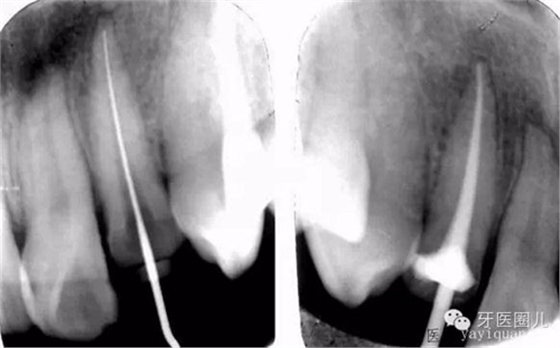

前牙折斷的前牙長(zhǎng)可以一次性完成治療:

患者外傷11 21簡(jiǎn)單冠折,選擇一次法完成冷牙膠充填3天后行樁修復(fù)。

一次法充填后最嚴(yán)重的疼痛發(fā)生在治療后24小時(shí)內(nèi),也有文獻(xiàn)說(shuō)是6-8個(gè)小時(shí),隨后患者反應(yīng)會(huì)大大減輕,與多次法比較治療的并發(fā)癥和成功率沒(méi)有差別,這個(gè)病例次日電話回訪患者患者無(wú)不適。